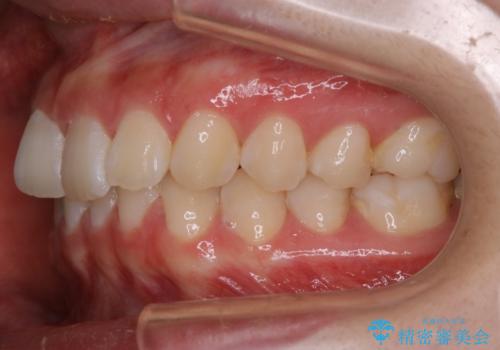

- 初診時、前歯のガタつきを主訴にご来院されました。

精密検査の結果奥歯の噛み合わせのズレからくる前歯のガタつきであることが分かり、患者様と相談した結果、全体をしっかりと治療することをご選択なさったので奥歯から動かして噛み合わせと見た目の両方を治す治療プランとなりました。

下顎の歯は幸いガタつきが少なかったため、下顎を基準とし構成する方針としました。

初診時の写真では一見噛み合わせには問題がないように見えても、実際に精密な検査を行うと改善すべき点が見つかる場合も多くあります。

当院では、矯正治療は見た目の改善が主目的ではなく機能面を改善し自然に長持ちする口腔内環境を整えることに重きを置く必要があると考えます。

しかしながら、こちらの理想だけを押し付けるだけが良い治療とは言えないので、患者様と治療のゴールの設定をよく話し合ったうえで方針を決定していくことが最も重要です。